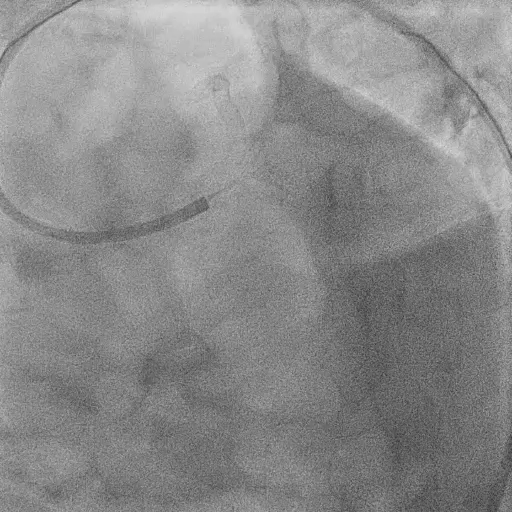

Pre-DK Crush PCI

Identified severe stenoses at distal LM, ostial LAD, ostial LCX, LAD at ostial D1, LAD, and LCX.

After Predilation with 2.0 mm SCB, check IVUS at Distal LM, Ostial LCX, Ostial LAD, and LAD at Ostial D1 level.

Predialation at LM-LAD with 3.0/15 mm NCB (high pressure) and LM-LCX with 3.0/15 mm NCB (high pressure).

Due to dissection at Ostial-Proximal LCX, decided to perform 2-stent strategy (DK - crush).

During DK-Crush PCI